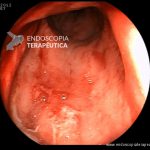

- Doença de Crohn em remissão – cicatriz